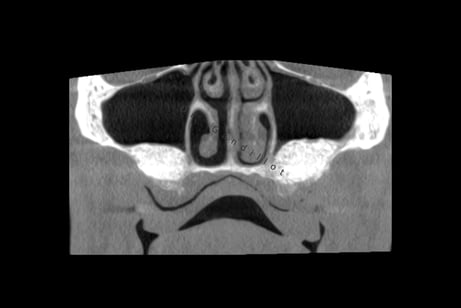

Les sinus sont des cavités dans l’os du massif facial, au-dessus des prémolaires et des molaires.

Après extraction des prémolaires et molaires maxillaires, la hauteur osseuse disponible sous le sinus maxillaire n’est souvent pas suffisante pour insérer un implant dentaire.

Il est nécessaire de surélever le plancher sinusien, cette procédure est également appelée sinus lift ou greffe osseuse sous-sinusienne.